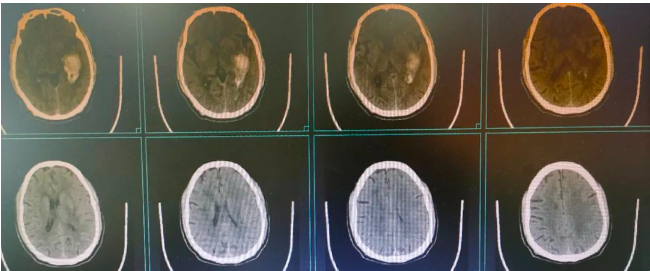

近日医院神经外科一患者,男性,59岁,因“突发头痛、头晕5天,加重伴恶心、呕吐3天”入院,入院查体: BP:162/93mmHg 一般情况及精神差,神志清楚,言语利索,双瞳等大同圆,直径约3.0mm,光反射存在, 四肢肌力正常,生理反射存在,病理反射未引出。门诊头颅CT提示左侧颞叶脑出血,并周围水肿形成。